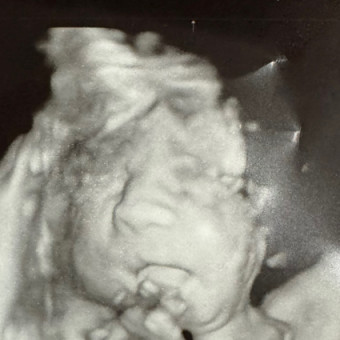

Baby boy’s registry🩵

Ashley Duran

March 22, 2025